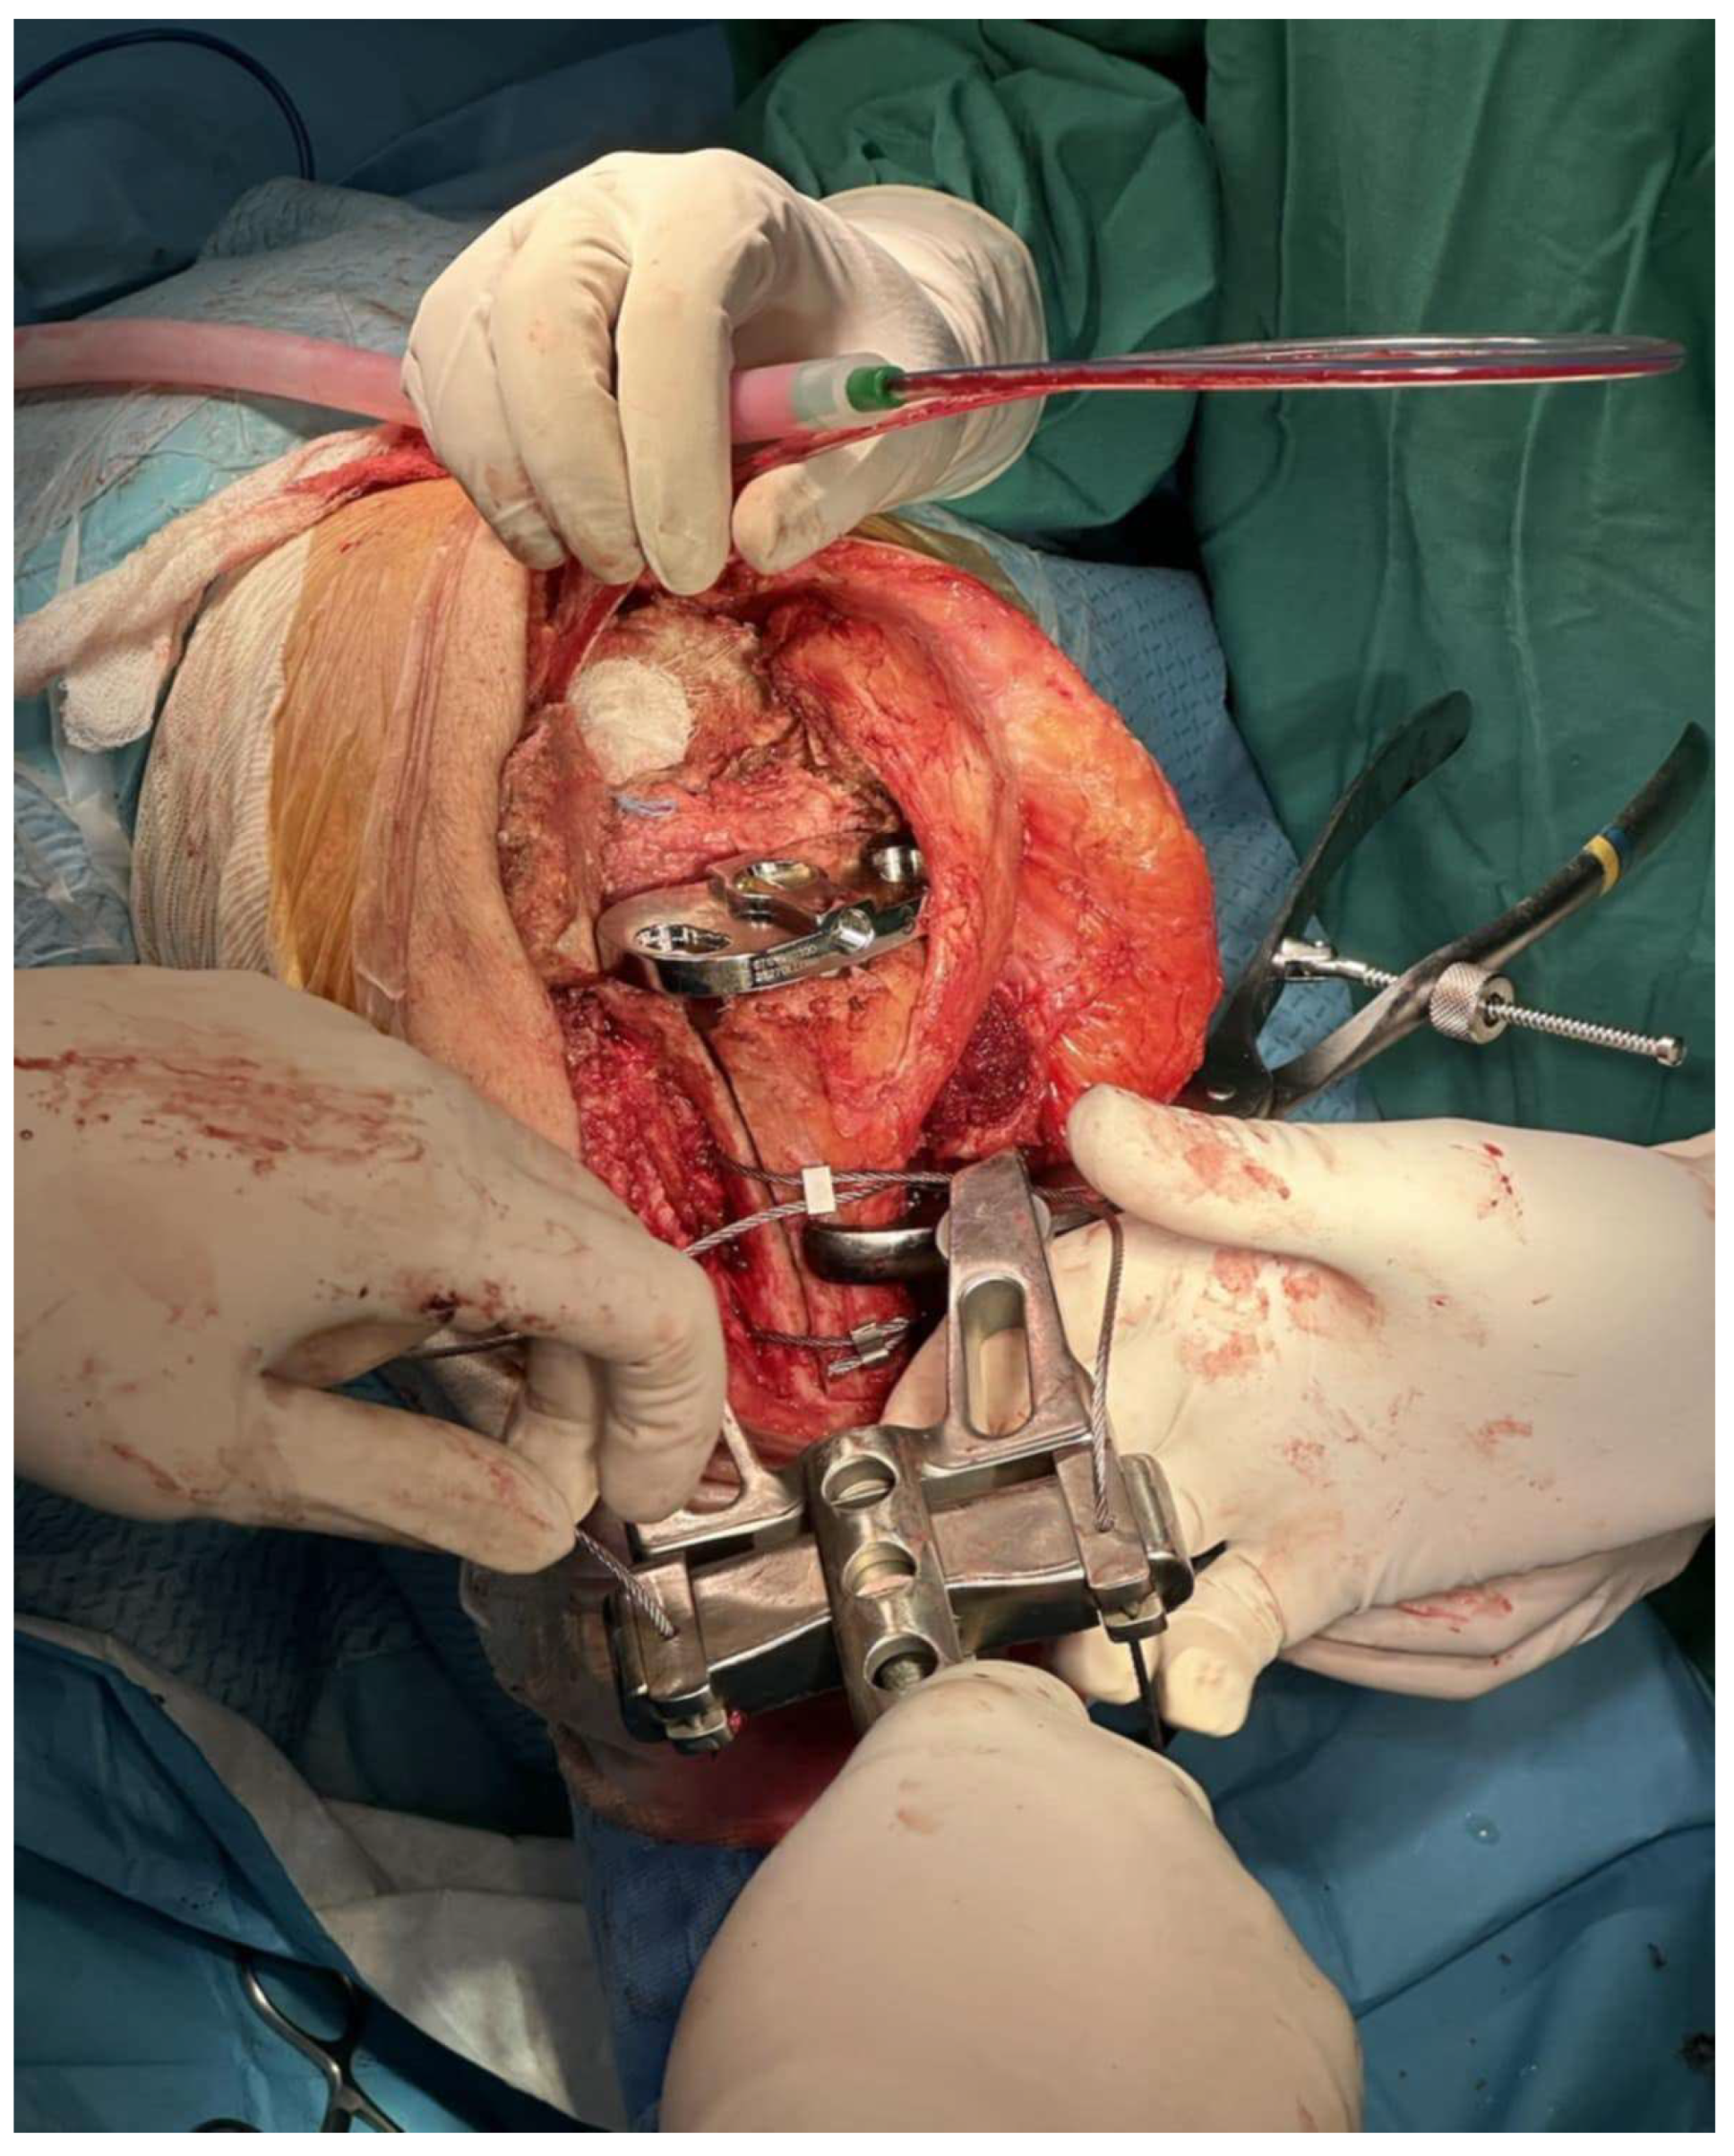

Figure 5. Intraoperative photograph after extended tibial tuberosity osteotomy demonstrating tibial stem malposition with cortical perforation. Final construct after osteotomy reduction with the use of three cerclage wires and bone graft (Case 5).

We retrospectively reviewed seven (7) hemophilic patients, with a mean age of 57.5 ± 1.50 years (95% confidence interval: 56–60 years) and mean body mass index (BMI) of 26.07 ± 0.67 kg/m2 (95% confidence interval: 25–27 kg/m2), who underwent ETTO for revision TKA in our department between 2015 to 2023. Preoperative diagnosis included (a) aseptic loosening of the femoral component but with a well-fixed tibial stem in four cases and (b) tibial component malposition that caused marked axial deformity in three cases (Figure 5). All seven patients initially considered for the study were included in the final analysis. None met the exclusion criterion—namely, the presence of active infection—at the time of evaluation, and all subsequently underwent surgery. The same surgical technique was applied in all seven cases. In Case 5 (Figure 5), the ETTO fragment was augmented with a bone graft prior to final reduction using cerclage wires, due to a bone defect attributed to prior stem perforation. A rotating hinge prosthesis was implanted in all patients, with an uncemented long stem. Clinical and radiological evaluation was performed at 6 weeks and 3, 6, and 12 months after surgery. Full baseline characteristics and outcomes are described in Table 1, Table 2 and Table 3.